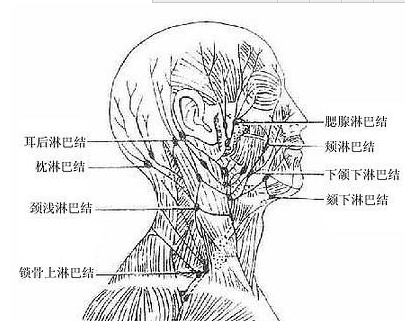

發病部位:

淋巴系統

慢性淋巴結炎圖片

慢性淋巴結炎 (31)